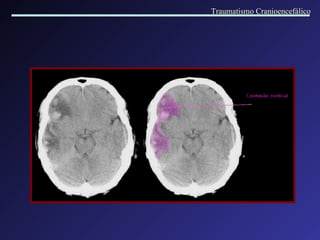

Contusão; concussão Dano após golpe contra a cabeça, onde o encéfalo desliza sobre o crânio produzindo lesões por atrito contra a superfície óssea. Traumatismo Cranioencefálico

Hematoma intracerebral  Contusão hemorrágica   Traumatismo Cranioencefálico

Contusões múltiplas e hematomas intracerebrais Densidade mista: múltiplas áreas de hemorragia com edema perilesional. Traumatismo Cranioencefálico

Hematoma intracerebral  Contusão hemorrágica multifocal Múltiplos pequenos focos hemorrágicos localizados em torno de vasos sanguíneos, no espaço de Virchow- Robin. Traumatismo Cranioencefálico